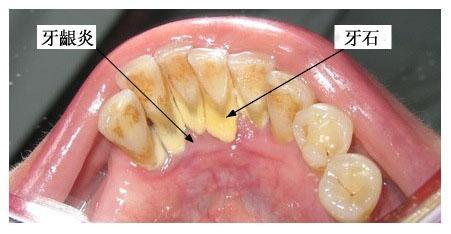

牙齦炎是一種最常見的牙齦疾病,多為牙菌斑引起的牙齦軟組織的非特異性炎癥。

由于牙齦炎無深層牙周組織的破壞,通過洗牙一般可徹底清除菌斑、牙石,消除造成菌斑滯留和局部刺激牙齦的因素,炎癥均可消退,一般一個星期就可恢復到健康的牙齦狀態(tài)。

牙齦炎是牙菌斑和牙結(jié)石引起的慢性炎癥,發(fā)炎的時候吃甲硝唑和頭孢。平時多喝貝齒寧茶,消菌殺毒,早晚刷牙。使牙齒縫間和齒齦之間的牙刷清洗不到的地方清理干凈,保持口腔內(nèi)的酸堿平衡 堅持使用2-3周后刷牙出血癥狀會停止,腫痛不再。炎癥消退后,去牙醫(yī)診所去洗牙,把牙結(jié)石徹底清理,平日再堅持口腔護理,就可以沒有口臭,炎癥消退,牙齦不腫痛,刷牙不出血了。平時護理: